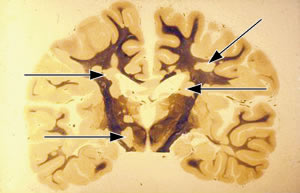

| 日本で最初に発見された患者さんの脳を前から見る。1965年に死亡し京都府立医大の米沢博士が解剖。矢印が病巣 |

日本で最初の患者さんが確認されたのは1965年です(写真)。増加の原因はわかっていませんが、衛生状態が改善して幼少期に感染症にかかることが減ったことと、日光(紫外線)にあたる機会が減り、体内でつくられるビタミンDが少なくなったことで、自分の神経組織を攻撃する異常な免疫を抑えられなくなったと考えられています。